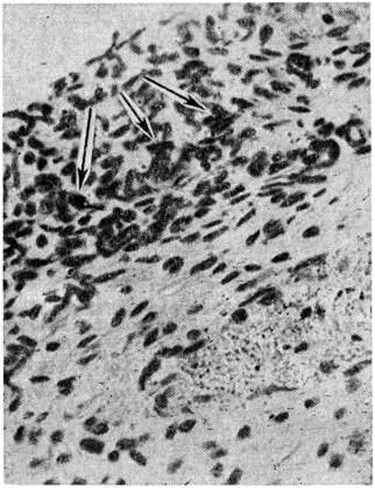

Рис. 1.

Микропрепарат стенки тонкой кишки при коли-энтерите: выраженная лейкоцитарная инфильтрация в подслизистой основе кишки (указана стрелками).

При Коли–инфекция в ряде случаев, кроме нейроваскулярных и дистрофических изменений, наблюдается также пролиферация клеток стромы слизистой оболочки и очаговая воспалительная инфильтрация подслизистой основы кишки лимфогистиоцитарными элементами с большей или меньшей примесью полинуклеаров (рисунок 1). Для обнаружения воспалительных очагов необходимо исследовать кишку на большом протяжении, так как процесс развивается в местах наибольшего скопления бактерий и токсинов.